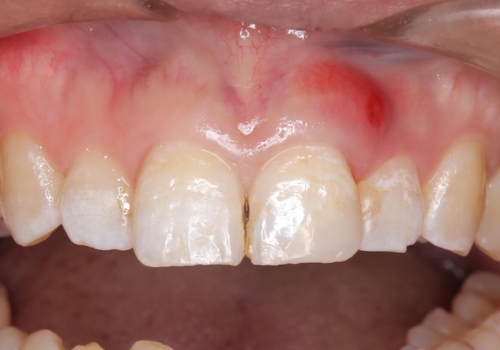

- 定期的に当院に通院されている患者様ですが、前歯が欠けてしまい困っているとのことで来院されました。その日は応急でレジン充填を行いましたが、上下顎前歯の当たりが強くまた同じように欠けてしまう可能性が高いと考え、セラミッククラウンにて修復した一例です。前歯一歯の色合わせは非常に難しく、特に周囲の歯に模様がある場合難易度が上がります。そのため、今回は当院のセラミッククラウンの中で最もランクの高いものを選択し、非常に綺麗に仕上げることができました。